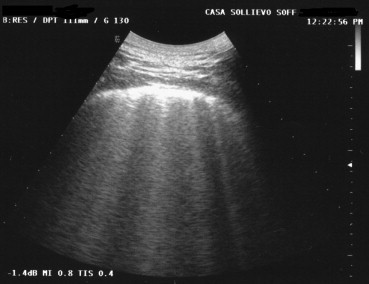

Fig. 2.

Reverberation artifacts (concentric, horizontally oriented, hyperechoic lines that represent the pleural-thoracic wall interface) in a normal subject.